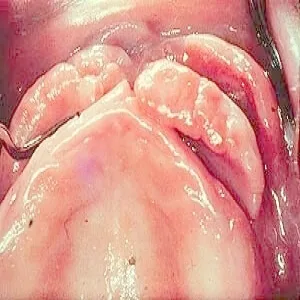

Nadziąślak

Nadziąślak, epulis